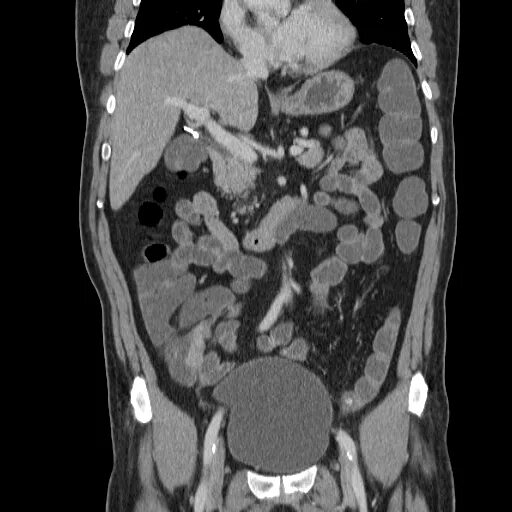

Рак прямой кт